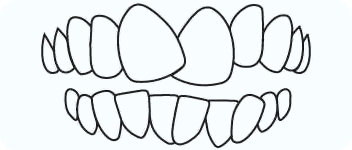

Cross Bite

In a crossbite, one or more of your lower teeth overlap the outer surface of your upper teeth. Crossbites can occur in front or back teeth.